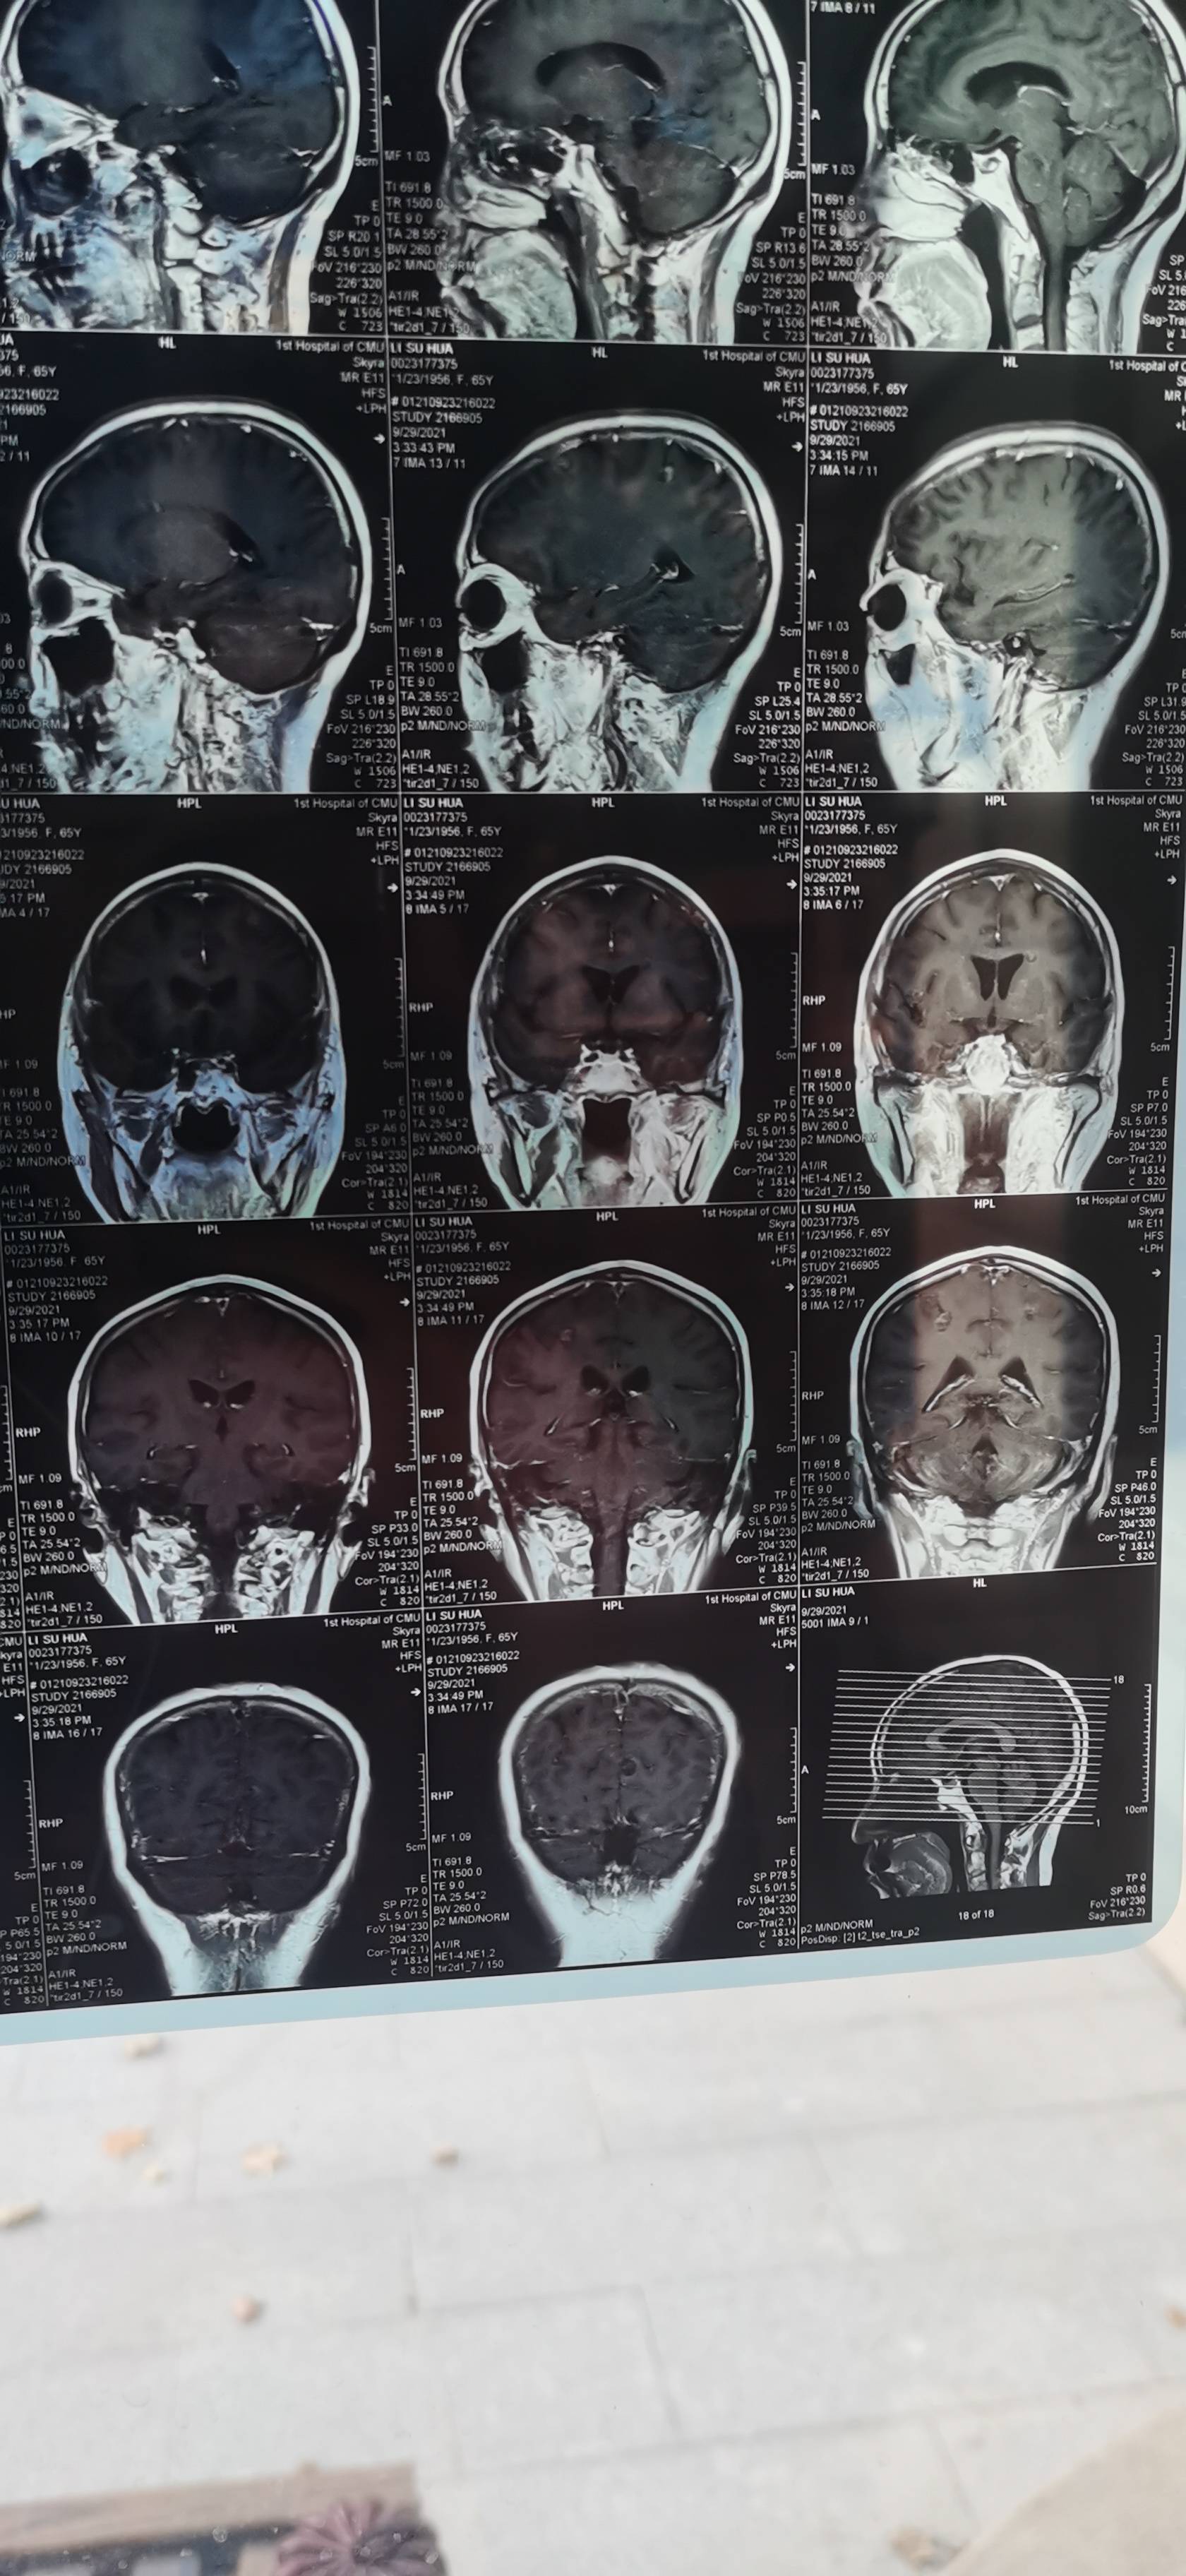

谢谢大家的建议,找到专家看片子了,专家的意见,不是脑膜转移,因为有一个肿瘤离脑干近,做射波刀的时候肯定多少有影响,而且症状也很像脑干受损,让我们观察,目前没有进展,这几天说话比之前利落了,走路不稳也有改善。